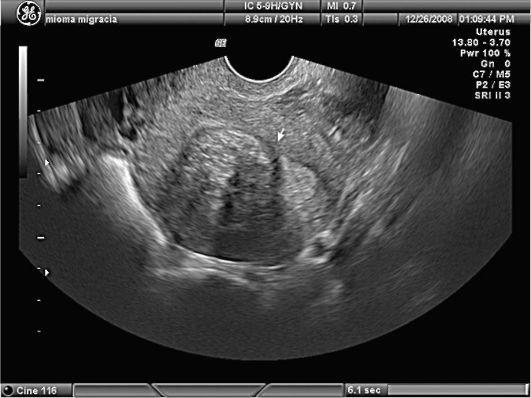

Ультразвуковое исследование при миоме

Наиболее распространенный метод диагностики и последующего наблюдения при миоме матки, который позволяет определить локализацию, величину узлов, деформацию полости матки, патологические изменения эндометрия.

Роль УЗИ в распознавании сарком ограничена, поскольку четких акустических признаков саркома не имеет. Однако увеличение размеров опухоли при контрольном исследовании (увеличение опухоли за год на величину, соответствующую 5-недельному сроку беременности, считается быстрым ростом опухоли), изменение структуры фиброматозного узла в сочетании с клиническими проявлениями в перименопаузе и в постменопаузе является показанием к хирургическому лечению. УЗИ исследование так же позволяет оценить состояние соседних органов и регионарных лимфоузлов.

По данным УЗИ можно заподозрить саркому матки на основании неоднородной эхогенности и узловой трансформации матки, участков с нарушением питания и некрозом в узлах. Появляется патологический кровоток со снижением индекса резистентности при допплерографии ниже 0,40.

УЗИ органов малого таза и забрюшинных лимфатических узлов. Ультразвуковыми признаками саркомы являются неоднородная эхогенность новообразования, присутствие некротических участков, уменьшение индекса резистентности в сосудах опухоли, обнаружение патологического кровотока в режиме допплерографии;